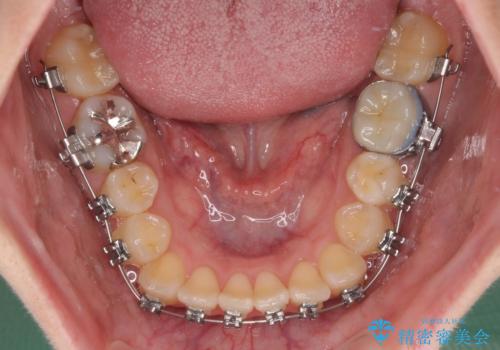

- 矯正装置

- メタルブラケット

- 前歯のクロスバイトを改善したいとのことで来院された患者様です。

マウスピース矯正では前歯の神経への負担が大きいことを懸念され、ワイヤー装置による矯正治療を行うこととしました。

クロスバイトが改善する際は、前歯しか接触しないため、痛みがあったり食事が取りにくかったりと、不便な時期がありますが、1年強の短期間で無事に治療を終えることができました。